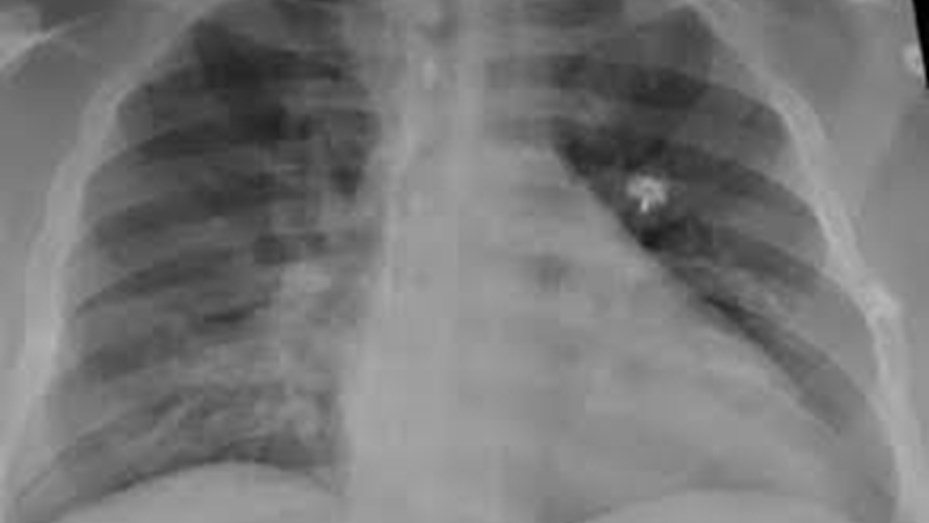

La neumonía bilateral “es una de las mayores complicaciones de los pacientes con Covid, es una enfermedad que afecta los dos pulmones. En casos graves debe internarse y a veces puede ser causa de muerte”, alerta Ana Putruele, jefa de la División de Neumología del Hospital de Clínicas.

En la actualidad este tipo de neumonía en general se ve en casos de coronavirus y constituye el 80% de las internaciones. También se presenta en menores de 2 años ,en mayores de 65 y en portadores de enfermedades crónicas, cardíacas y asociadas a tabaquismo suele generar riesgo de mortalidad llevando a insuficiencia respiratoria severa o distress respiratorio que requiere de oxigenoterapia o si es muy grave asistencia respiratoria mecánica”, comenta la profesional.

La neumonía es la sexta causa de muerte en nuestro país y sumado a las complicaciones que causa en enfermos con Covid-19 pueden dejar secuelas crónicas o incluso llevar la muerte al paciente.